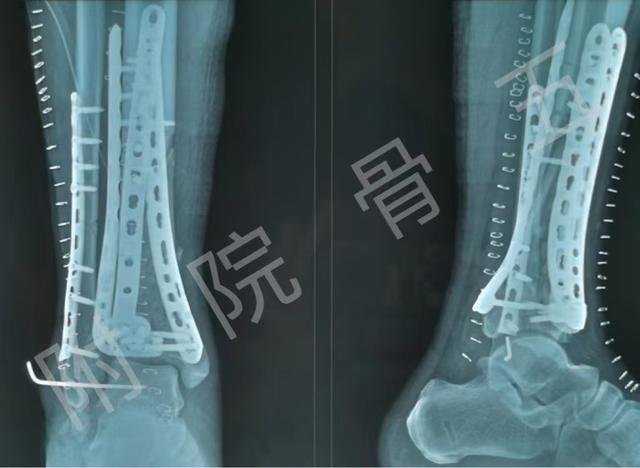

2022年5月,河北工程大学附属医院骨五科主任贺靖澜带领其团队成功应用3D打印技术治疗了一例右踝关节开放性骨折伴脱位(Pilon)的患者。

患者张某,因高能量创伤致右踝关节粉碎骨折伴脱位,入院后积极完善相关检查。由于创伤较重,患处肿胀明显,骨折粉碎严重,骨五科贺靖澜主任立即组织医生们讨论治疗方案。应用3D打印技术辅助骨科手术,通过术前3D打印模型进行骨折分析和模拟手术,使得手术按照原先术前计划进行。

骨五科贺主任介绍:传统的骨科手术仅仅根据影像学结果及手术医生的临床经验实施,不仅操作不够精准,而且创伤大、手术时间长,而1:1的3D打印技术造出的模型,可以提前设立手术入路,内固定物测量,术前可在模型上预先模拟过复位步骤,更准确更直观,这一系列术前准备为手术节省了时间,并减少了术中失血,进一步降低了手术风险,提高了手术的精准性。